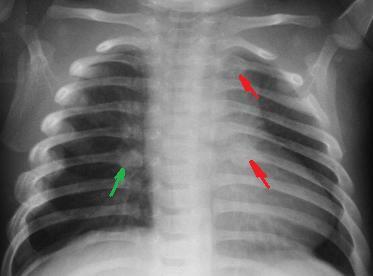

Переломы ребер обычно диагностируются на рентгенограмме грудной клетки, и тяжесть перелома легко видна. Простые (без смещения) переломы проявляются трещинами в ребре или неровным краем. Переломы со смещением не имеют контура вдоль края ребра на рентгенограмме. Плавающие сегменты ребер, известные как цепная грудная клетка, также можно легко увидеть на рентгеновском снимке. Другие методы визуализации, такие как компьютерная томография, также диагностируют переломы ребер и являются более чувствительными для их выявления.Компьютерная томография полезна для определения наличия основного повреждения легких, известного как ушиб, или для определения выхода воздуха из легких в виде пневмоторакса.

- Окончательный диагноз устанавливается по результатам рентгенографии грудной клетки, при которой помимо наличия перелома ребер можно также выявить пневмоторакс — скопление воздуха в плевральной полости со сдавлением легкого.